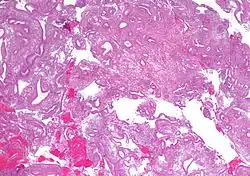

| Micrograph showing simple endometrial hyperplasia, where the gland-to-stroma ratio is preserved but the glands have an irregular shape and/or are dilated. Endometrial biopsy. H&E stain. | |